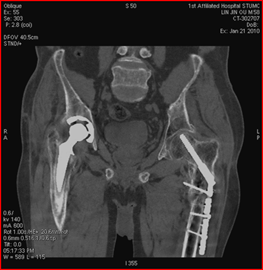

高能量X射线可以去除高密度金属引起的伪影

常规CT 宝石能谱CT

140keV能量成像可以除去金属引起的伪影,更加清晰观察术后情况